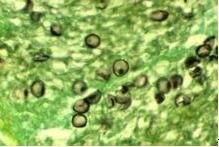

一、發(fā)病特點:肺孢子菌病是由卡氏肺孢子菌引起的呼吸系統(tǒng)機會感染?ㄊ戏捂咦泳w寄生在肺泡內(nèi),其臨床特征為發(fā)熱、于咳、呼吸急促、呼吸困難和發(fā)紺等,癥狀呈進行性加劇,

卡氏肺孢子菌

病死率高?ㄊ戏捂咦泳鷱V泛存在于人和某些哺乳類動物肺組織內(nèi)。隱性、亞臨床或潛在性感染相當(dāng)多見。血清流行病學(xué)調(diào)查顯示多數(shù)健康兒童幼年曾與原蟲接觸,2/3以上可檢得IgG抗體;與病人接觸的醫(yī)務(wù)人員中7%~15%抗體效價升高。病人和隱性感染者為本病傳染源,主要通過空氣飛沫傳播。健康人感染后一般不發(fā)病,本病呈世界性分布。